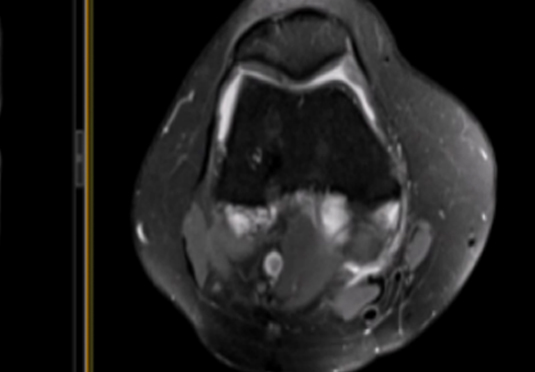

組織破壞和浸潤:侵襲和破壞正常組織,穿過正常組織的屏障,入侵到其他組織和器官中,形成遠(yuǎn)處的轉(zhuǎn)移,顯示出惡性腫瘤細(xì)胞的擴(kuò)散能力。